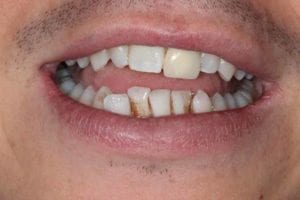

Trauma to Upper Front Teeth

Both central incisors were broken, leaving just the roots. Unfortunately, there wasn’t enough tooth to repair these teeth and they were subsequently removed. Dental implants were placed to restore the missing teeth.